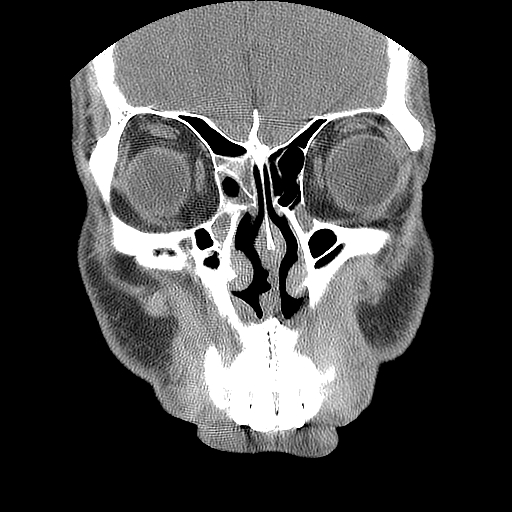

男,38岁,鼻塞、头痛2个月,要求鼻窦ct检查。

右侧上颌窦、蝶窦、筛窦、额窦及左侧上颌窦慢性炎症。

右侧鼻中隔左偏,右侧上颌窦、筛窦、额窦慢性炎性病变。右侧上颌窦开口粘膜增厚。

1)副鼻窦炎。2)右侧中鼻道及总鼻道粘膜息肉样变。3)双侧中下鼻甲肥大。4)鼻中隔轻度左突偏曲。